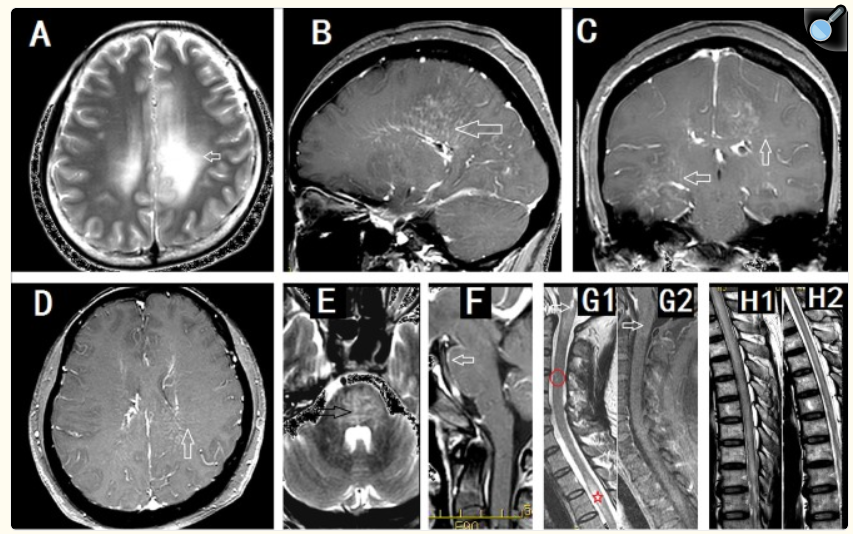

Astrocitopatía Glial Fibrilar